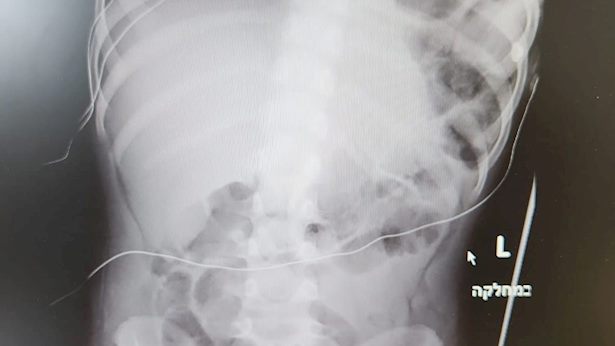

מספר ימים לאחר הגעתו למחלקת השיקום של בית החולים ספרא לילדים, החל הילד לחוות מצוקה נשימתית, מה שגרם לצוות הרפואי לנקוט בפעולה מהירה. צילום רנטגן גילה קרע בסרעפת - שריר חיוני לתפקודי הנשימה שאחראי על הפרדת חלל החזה והבטן. הצילום גילה ממצא מדאיג נוסף: בעקבות הקרע, איברי חלל הבטן פרצו לתוך החזה ופגעו ביכולתו של הילד לנשום כראוי.